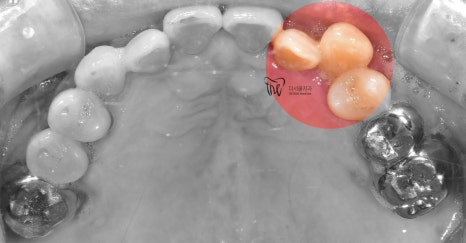

『개방교합 사진』

이 분은 과거 더서울치과에 찾아오셨던 분입니다.

치아 상태를 보면, 나이가 어느정도 있다는 것을

바로 직감할 수 있고, 딱 봤을 때 전형적인

개방교합 형태를 가지고 계셨었습니다.

여기서 크게 문제를 삼는다면,

1) 치경부 마모증 증세 확인

2) 잇몸이 내려가 있다

3) 구강 위생 관리가 전혀 되고 있지 않음

4) 개방교합

이렇게 3가지로 볼 수 있습니다.